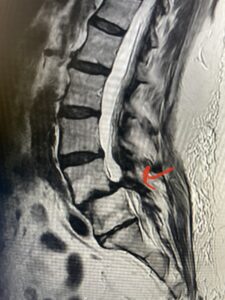

Fig 1: Sagittal T2-weighted lumbar MRI demonstrating grade 1-2 spondylolisthesis L4-5 with severe stenosis (red arrow)

Another patient is a 62 year-old female with progressive low back pain and right leg pain and numbness that radiates to the top of her foot. She tried physical therapy and epidural injections. MRI demonstrated severe L3-4 stenosis and a grade 1 spondylolisthesis (Fig 4). There was L5-S1 and L4-5 disc collapse with modic end-plate changes. Biomechanically because of the significant degeneration of these disc spaces which stiffened the L4-S1 segment more stress was placed on the L3-4 segment, resulting in significant premature degeneration and compensatory stenosis and segmental instability. The MRI also showed pathologically, because of the slip, the L3 inferior processes were more anteriorly oriented and hence contributing to the majority of the lumbar canal compromise. Note the more sagittally-oriented facets in this case compared to the prior case (Fig 5). The patient underwent a decompressive laminectomy with attention of removing the inferior processes of L3 to fully decompress the canal. We also performed an L3-4 fusion with instrumentation (Fig 6). The patient had an uneventful postoperative course with improvement of leg pain. Of note with relief of the disabling leg pain patients are generally very happy. Patients can often manage their low back pain; it is the leg pain that they just can’t tolerate.

Fig 4: Sagittal T2-weighted lumbar MRI demonstrating L3-4 grade 1 spondylolisthesis with severe stenosis (blue arrow)